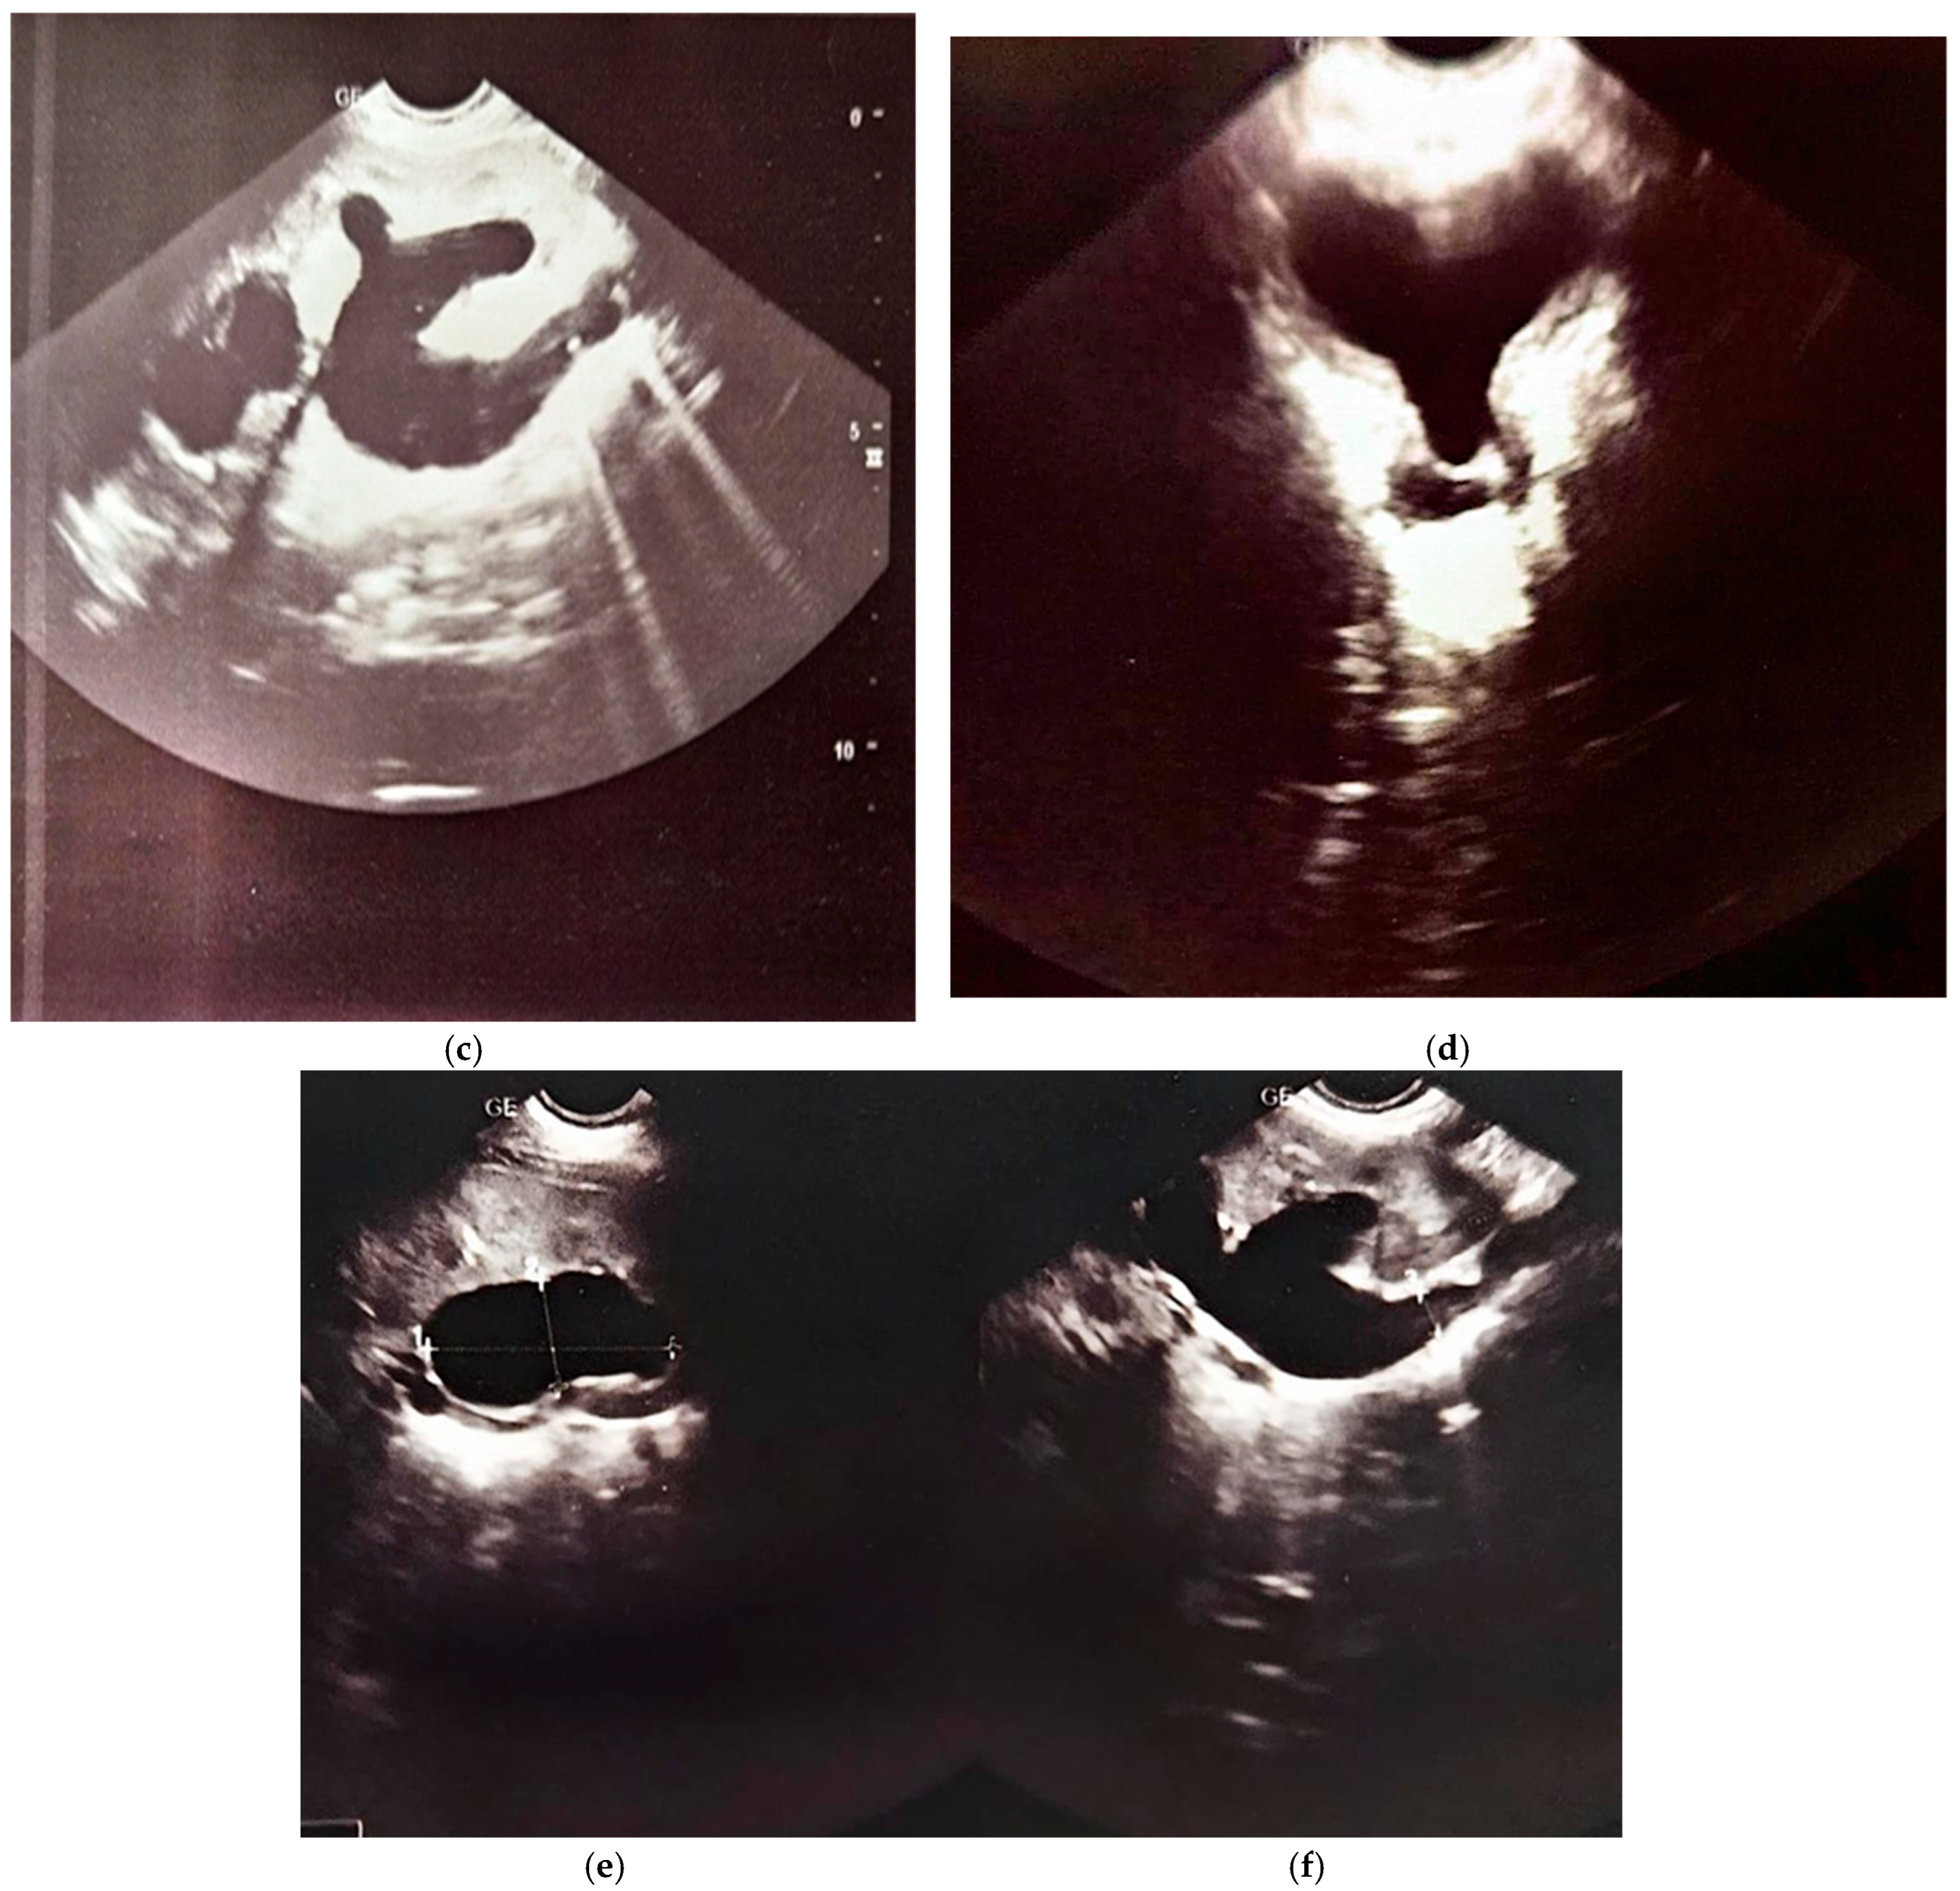

The third scintigraphy, performed when the patient was 2 years and 3 months old, revealed an enlarged left kidney with regular contours, normal perfusion, and homogeneous parenchymal uptake. The GFR was 148 mL/min. Excretion was spontaneous but slow and reduced until diuretic administration. Persistent stasis was noted in the pyelocaliceal and ureteral systems, with a tortuous ureter. The renogram indicated a normal parenchymal peak at 3 min, an excretory plateau with a maximum at 18 min, and delayed T1/2 at 55 min with increased residual activity. Post-diuretic T1/2 normalized, but stasis persisted.

The right kidney remained hypoplastic, with reduced perfusion, heterogeneous parenchymal uptake, and a GFR of 52.9 mL/min. Excretion was slow and reduced, with pyelocaliceal stasis. The renogram showed a delayed and flattened peak, a plateaued excretory segment with a delayed descent, and increased residual activity. Post-diuretic T1/2 normalized, but mild intrarenal stasis persisted.

The differential functional contribution was 72.1% for the left kidney and 27.9% for the right kidney, with a total GFR of 200.9 mL/min. The findings confirmed a hypoplastic right kidney with reduced function and a hypertrophic left kidney with post-diuretic-responsive ureterohydronephrosis (Figure 6).

Figure 6.

The third renal scintigraphy.